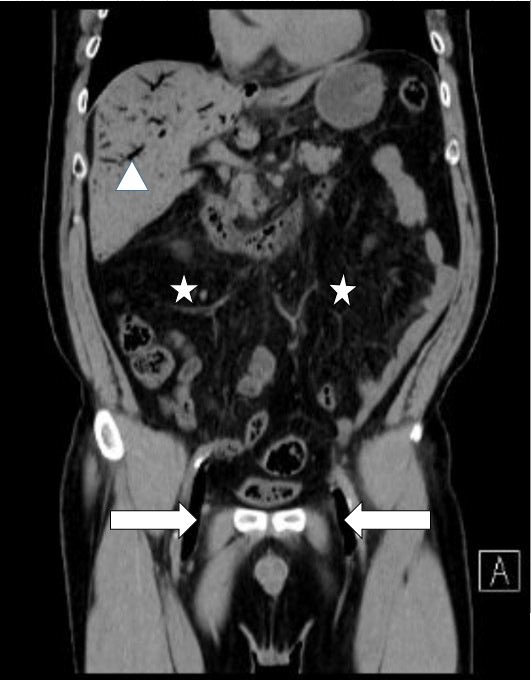

CT上門脈内、両大腿 静脈に空気塞栓、 さらに腸管壁周囲にびまん性の気泡が検出され(図1)、

図1 : 来院時腹部 CT

矢印:大腿静脈内の気泡  星印:腸管壁に気泡著明  矢頭:門脈内に空気塞栓